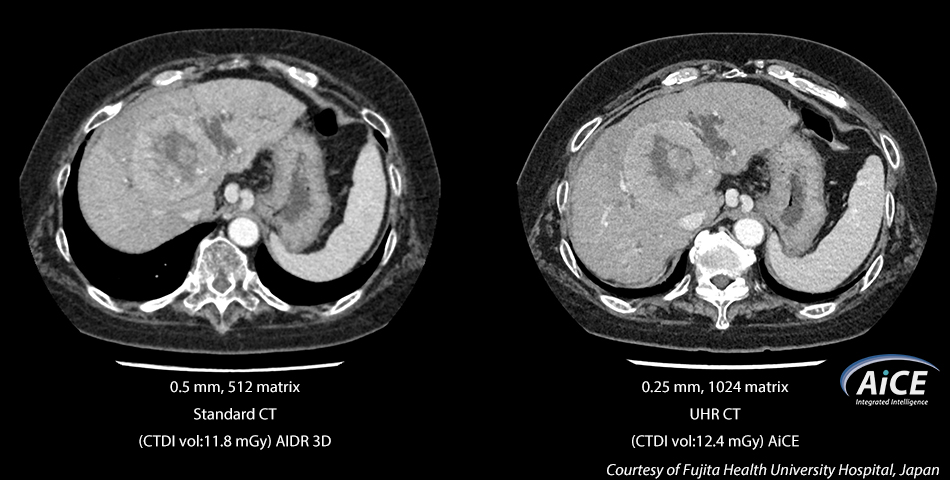

Known as AiCE, this deep learning reconstruction network is trained on an advanced Model-Based Iterative Reconstruction (MBIR) algorithm to produce low noise, and 0.25 mm, 1024 matrix Ultra-High Resolution CT images.

The Aquilion Precision introduces a revolutionary approach to CT reconstruction that leverages Deep Learning Neural Networks specifically trained to perform one task – reconstruct images that are sharp, clear, and distinct. Known as AiCE, this deep learning reconstruction network is trained on an advanced Model-Based Iterative Reconstruction (MBIR) algorithm to produce low noise, natural texture, and 0.25 mm, 1024 matrix Ultra-High Resolution CT images several times faster than clinical MBIR today.